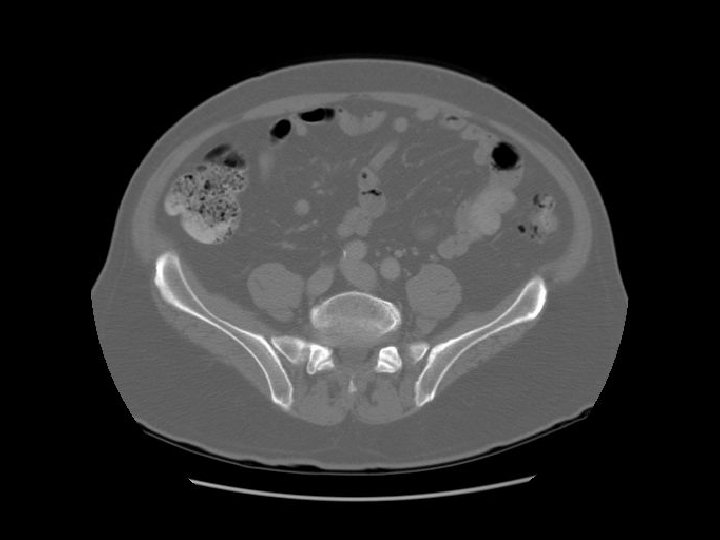

Rectosigmoid Sacroiliac joint

Diverticula in recto sigmoid Rectosigmoid

Arrows are pointing to air filled diverticulum and the second one is filled with residual barium from an old GI study.